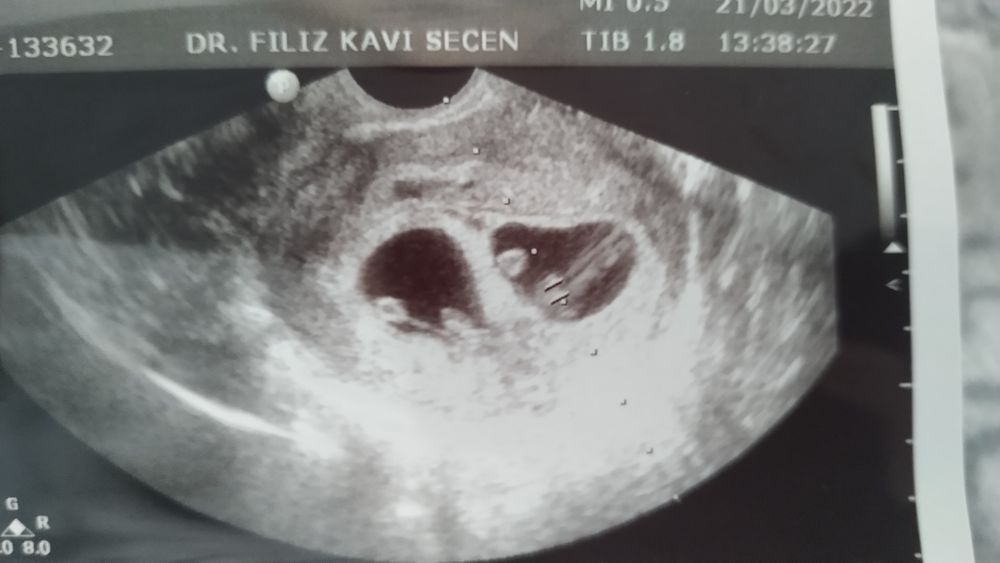

Итог стимуляции

Девочки спасибо большое ♥️ теперь столько мыслей в голове, даже не верится что это реально. Столько стресса пережила из-за войны. Мои сладкие бусинки, такие сильные. Верю в них что все будет хорошо 💞